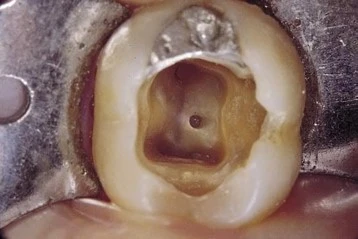

Những sai sót trong mở tủy: Mở tủy chưa đủ

Gồm: lỗ mở tủy quá nhỏ hoặc chưa mở hết trần tủy

trưa mở hết trần tủy

Khắc phục: mở rộng thêm lỗ mở tủy hoặc sâu xuống để phá bỏ hoàn toàn trần tủy

mở rộng trần tủy

loại bỏ hoàn toàn phần tủy trên